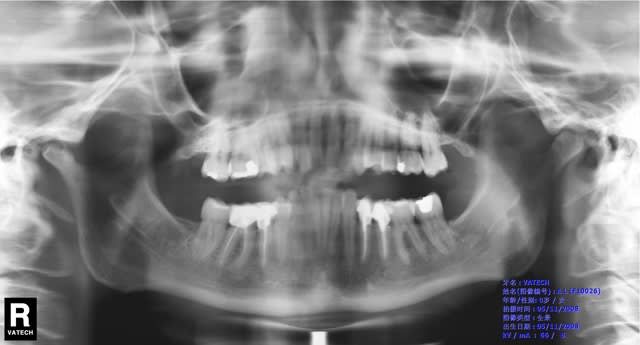

J'ai reçu une patient 35 ans, qui se plaint d'une forte douleur à l'ouverture coté droit au niveau de l'ATM depuis 1 mois.

Pas de claquement, crépitement , le trajet d'ouverture est droit, douleur à la palpation de l'ATM, à l'ouverture , la propulsion et latéralité gauche; l'ouverture est limitée par la douleur.

Elle est en classe II2, elle a eu un traitement d'ortho ancien, aucun traitement récent , les couronnes ont été refaites en 2006.

La PIM est normale il y a guidage antérieure en latéralité pas de verrou antérieure comme c'est souvent le cas avec les classe II2, pas de prématurité.

Il y a une image à l'apex de 46 mais aucun symptomes à la percussion ou palpation.

Pas de bruxisme ni trace d'usure importante, La PIM est confortable.

L'ortho montre un sérieux et ancien problème musculaire : escalier, et c'est peu dire, entre les incisives/canines et le bloc des prémolaires/molaires. La cl II indique que le problème est étendu, au-delà des seuls élévateurs.

Elle arrive sans doute au bout de ce que sa compensation occlusale peut faire. Momentanément ou définitivement.

La 27 est egressée certes mais il n'y a pas de prématurité.

Sans dec', Comme les petits gribouillis qui sont sur le pano le montrent, je bosse en chine.